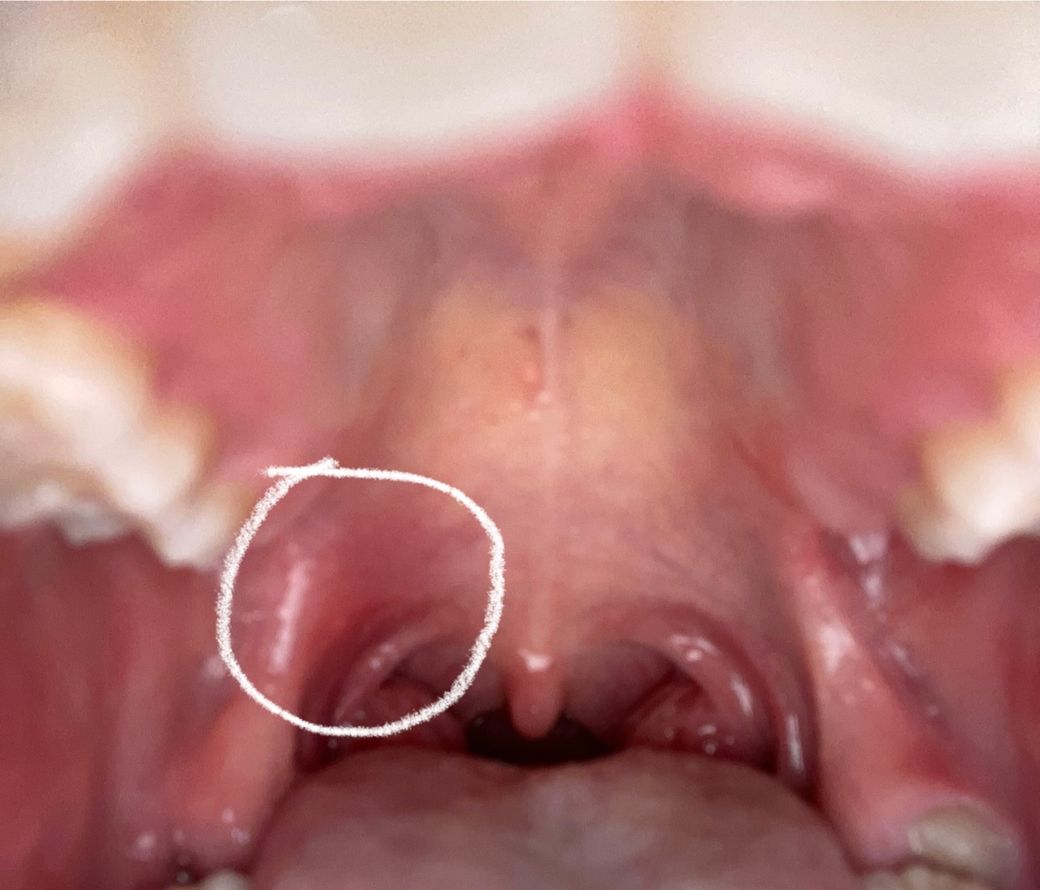

너무아파서 입을 제대로 못벌렸는데 편도에 작은알갱이 여러개있어요.. (누런? 흰?) 편도결석은 있어봤는데 그때랑 느낌이 달라요 ㅠㅠ 사진속 동그라미는 부운부분이고 오른쪽이랑 차이가 많이나요ㅠㅠ 편도염인가요?

사진상 동그라미 친부분 뒤로 포도송이처럼 부풀어 있는것이 편도가 염증으로 인해 부어 있는 것이고 편도염으로 진단이 가능합니다. 내과나 이비인후과 진료를 받으시고 적절한 약제 처방을 받으시기 바랍니다.